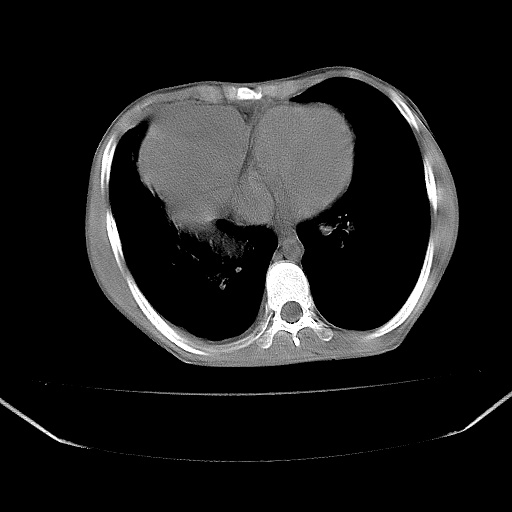

以下是引用zjzjr在2008-7-20 12:57:00的发言:[br]考虑为生殖源性肿瘤(内胚窦瘤),侵袭性胸腺瘤可能性大;右侧少量胸腔积液。

以下是引用xinliheng001在2008-7-20 21:17:00的发言:[br]右纵隔巨大分叶状软组织均质密度肿块,右上肺叶受压明显,纵隔右移、胸膜受累有少量积液和结节样增厚。应增强扫描一定会有更具诊断价值的信息。

以下是引用xinliheng001在2008-7-20 21:17:00的发言:[br]右纵隔巨大分叶状软组织均质密度肿块,右上肺叶受压明显,纵隔右移、胸膜受累有少量积液和结节样增厚。应增强扫描一定会有更具诊断价值的信息。